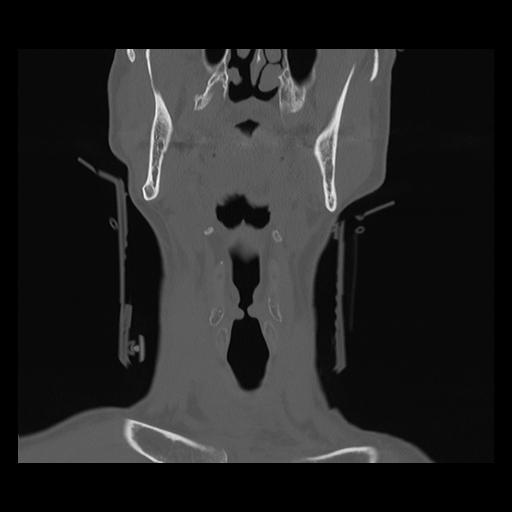

16 HUESO,,Coronal,2.000,HUESO,Coronal,